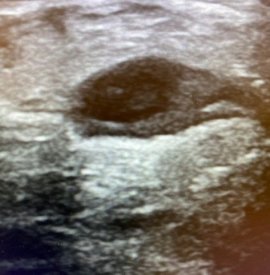

Resim. Baker kist rüptüründe bacak ve ultrason görünümü

Kist belirli büyüklüğe ulaştıktan sonra ani olarak yırtılabilir. Buna bağlı bacakta diz çevresinden başlayan ve aşağı doğru yayılan şişlik ve çok ciddi baldır ağrısı gelişir.

Bu ani gelişen şikayetler ile birlikte bacak arkasındaki kitle kaybolabilir. Bu tablo sıklıkla DVT ile karışabilmektedir. Bu hastalara yanlış tanı nedeniyle sıklıkla kan sulandırıcı iğneler başlanmaktadır.